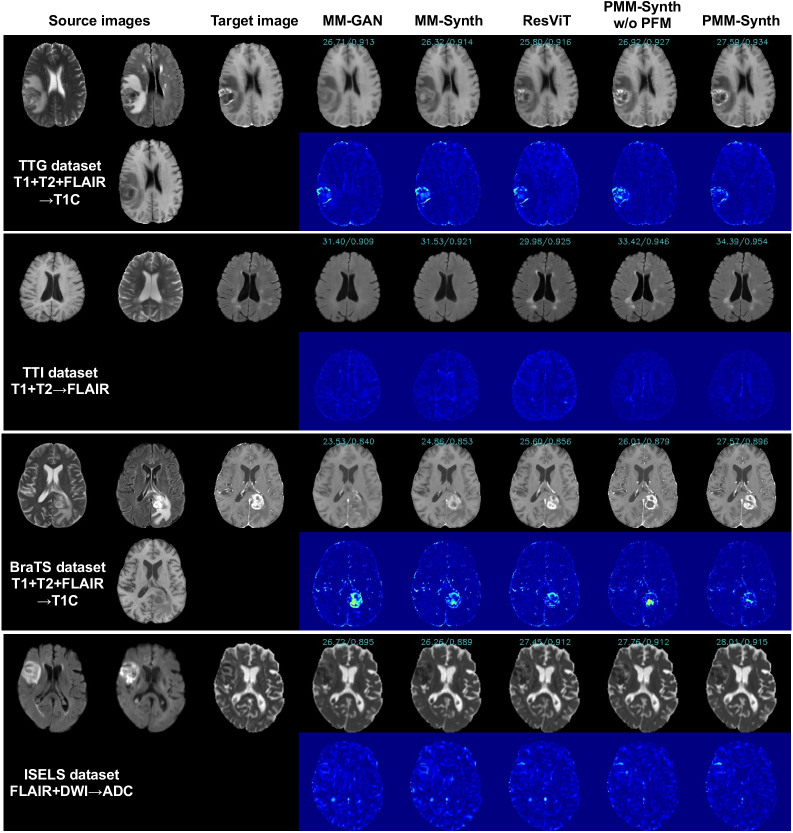

Refer to caption

(a) Qualitative comparisons of one-to-one MRI synthesis across heterogeneous datasets. Blue decimals denote PSNR/SSIM values.

(b) Qualitative comparisons of many-to-one MRI synthesis across heterogeneous datasets. Blue decimals denote PSNR/SSIM values.

Since pFLSynth and FTN are one-to-one synthesis models that do not support multi-modal inputs, we first select representative one-to-one synthesis tasks from each dataset for comparison. Specifically, we use T1\rightarrowT1C and T2\rightarrowFLAIR on the TTG dataset; T1\rightarrowT2 and T2\rightarrowFLAIR on the TTI dataset; T1\rightarrowT1C and T2\rightarrowFLAIR on the BraTS dataset; FLAIR\rightarrowDWI and FLAIR\rightarrowADC on the ISLES dataset. Quantitative and qualitative results of one-to-one tasks are presented in Table 1 and Fig. 2(a). Overall, three single-dataset methods exhibit obvious limited performance due to the restricted scale and diversity of a single training dataset. While FTN trained on multiple datasets achieves competitive quantitative performance, its synthesized images appear noticeably blurred and lack high-frequency details. Besides, FTN is fundamentally limited to one-to-one synthesis tasks and cannot accommodate multi-modal inputs, revealing its restricted task versatility. Through comparison, PMM-Synth yields the best quantitative results and generates the most visually realistic images across all four datasets. Especially, PMM-Synth generates clearer tumor enhancement and richer high-frequency details while competing methods often miss or oversmooth. For example, in the row of the TTG dataset in Fig. 2(a), MM-GAN, MM-Synth and FTN fail to enhance the tumor region, and pFLSyn produces inaccurate enhancement. In contrast, PMM-Synth preserves realistic texture and edge sharpness, yielding higher fidelity in pathological regions. Similar advantages are observed in the BraTS dataset, where PMM-Synth generates FLAIR images with sharper lesion contours and more clearer edema areas. Beyond capturing finer structural details, PMM-Synth also better preserves the intensity characteristics of the target modality, which benefits from its dataset-specific personalization strategy. As shown in the TTI dataset example in Fig. 2(a), removing PFM from PMM-Synth (PMM-Synth w/o PFM) leads to more obvious intensity shifts from the real image, particularly in white matter and ventricular regions. Such findings confirm that our complete model is robust to distribution variations across datasets and capable of learning dataset-specific characteristics.

Except for pFLSyn and FTN, all the other methods are capable of handling synthesis tasks with various input-output configurations. Therefore, we further compare and analyze their performance on many-to-one synthesis tasks. Specifically, we select T1+T2\rightarrowFLAIR and T1+T2+FLAIR\rightarrowT1C on the TTG dataset; T1+T2\rightarrowFLAIR and T1+T2+FLAIR\rightarrowADC on the TTI dataset; T1+T2\rightarrowFLAIR, T1+T2+FLAIR\rightarrowT1C on the BraTS dataset; FLAIR+DWI\rightarrowADC, FLAIR+ADC\rightarrowDWI on the ISLES dataset. Table 2 and Fig. 2(b) report the comparison results. PMM-Synth effectively leverages complementary information from multi-modal inputs to enhance image fidelity, and achieves the best quantitative scores and visual quality across all four datasets. For example, the T1+T2+FLAIR\rightarrowT1C task on the TTG dataset (in Table 2) outperforms the one-to-one T1\rightarrowT1C task (in Table 1) in all quantitative metrics, which is consistent with the expected benefits of multi-modal integration. Results across both one-to-one and many-to-one scenarios demonstrate that PMM-Synth consistently outperforms competing methods on heterogeneous multi-modal MRI datasets, highlighting its superior generalizability and dataset-level versatility.